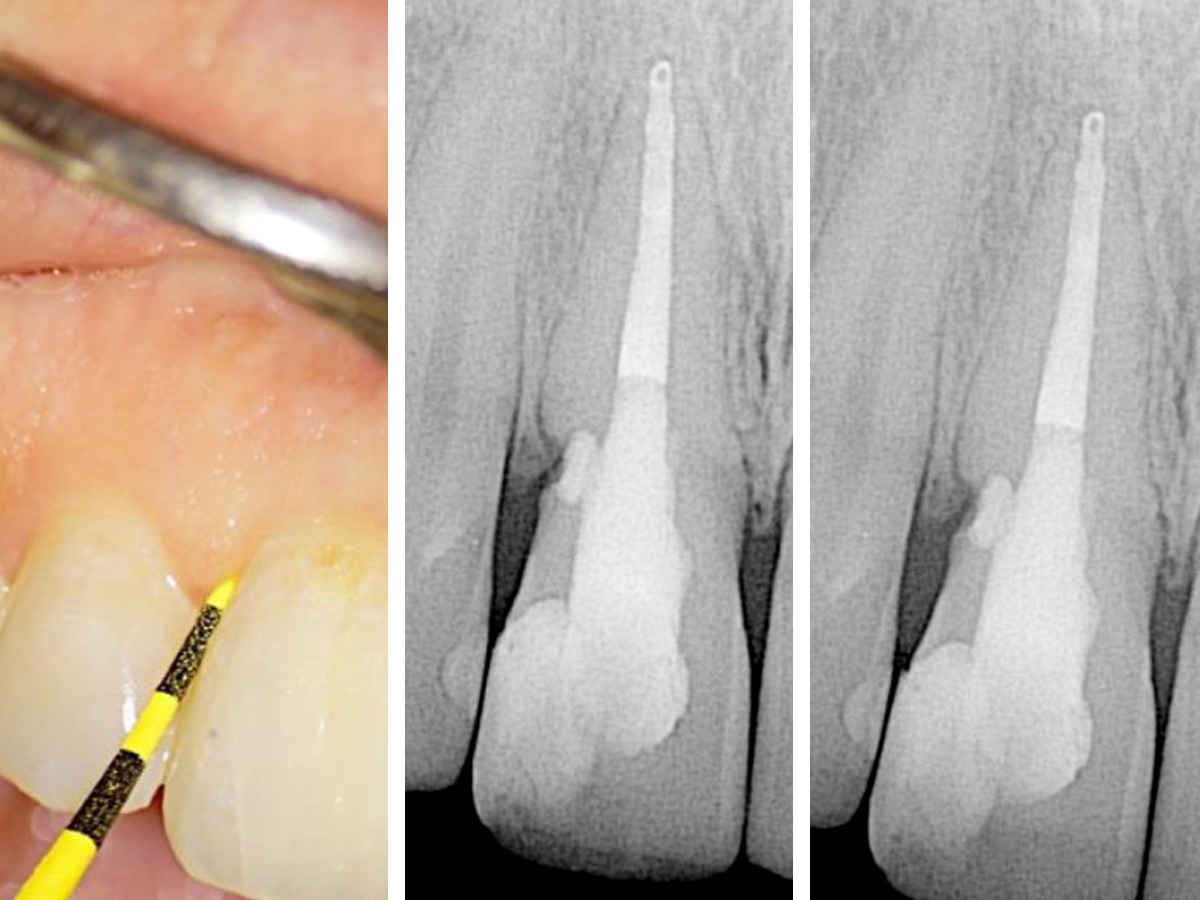

Abbildung 1

Klinische und röntgenografische Ansichten zeigen eine Fistelbildung, die bei genauerer Untersuchung zu einem distal liegenden, zervikalen Defekt an Zahn 11 führte.

Eine 29-jährige kaukasische Frau stellte sich mit Beschwerden an Zahn 11 vor, der wackelte und am Zahnfleisch Eiter aufwies. Ihre medizinische Vorgeschichte war irrelevant. Ihre zahnmedizinische Vorgeschichte beinhaltete eine Wurzelbehandlung, die 11 Jahre zurücklag. Der Zahn hatte sich etwa vier Jahre zuvor verfärbt und wurde mit Wasserstoffperoxid gebleicht. Die klinische und röntgenografische Untersuchung zeigte eine Fistelöffnung, die zu einem resorptiven Defekt im zervikalen Bereich des Zahnes führte (Abb. 1).